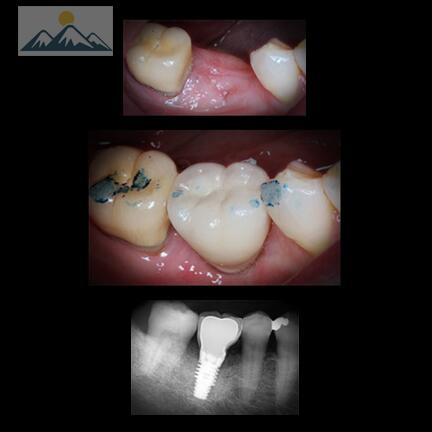

Out with the old, in with the new. This molar had a broken composite filling replaced. #lovemysmile

Old composite fillings replaced with new fillings on the back of the front teeth. #lovemysmile drchristophermorris.com/services/cosme…

Missing molar replaced with dental implant and crown. #lovemysmile